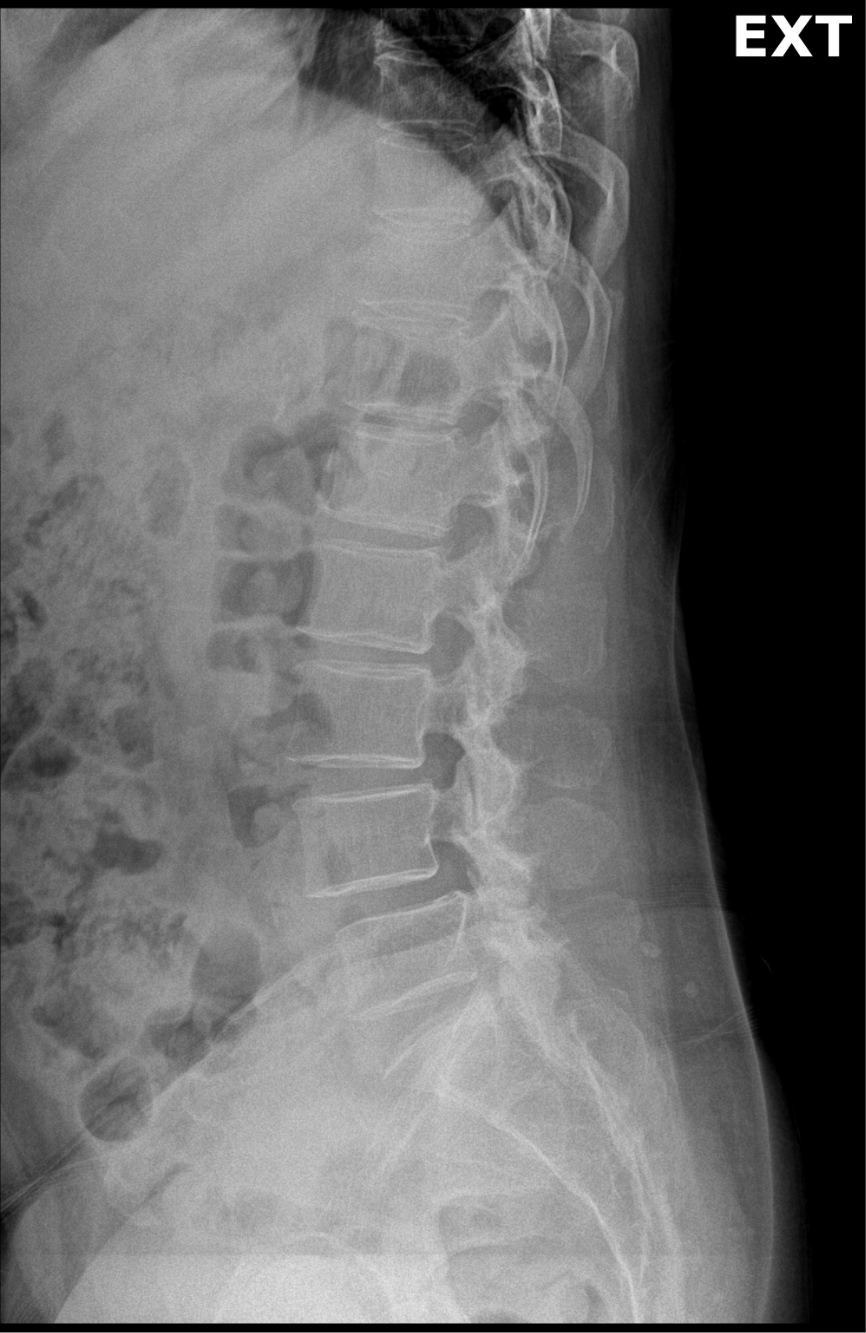

AP or PA